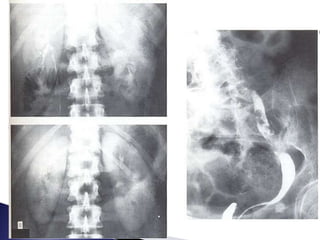

 El estudio radiológico debe iniciarse con la

radiografía simple de abdomen, que ofrece

información útil

◦ tamaño de las siluetas renales

◦ presencia o no de litiasis radio-opacas en áreas

renales, en teóricos trayectos ureterales o en área

vesical

◦ posibles lesiones metastásicas óseas o

desplazamientos anómalos de órganos vecinos

 Rx simple de

abdomen o de la

pelvis puede

mostrar la

presencia de

cálculos.

 El estudioradiológico debe iniciarse con la radiografía simple de abdomen, que ofrece información útil ◦ tamaño de las siluetas renales ◦ presencia o no de litiasis radio-opacas en áreas renales, en teóricos trayectos ureterales o en área vesical ◦ posibles lesiones metastásicas óseas o desplazamientos anómalos de órganos vecinos

 Rx simplede abdomen o de la pelvis puede mostrar la presencia de cálculos.  La ecografía es el procedimiento diagnóstico definitivo